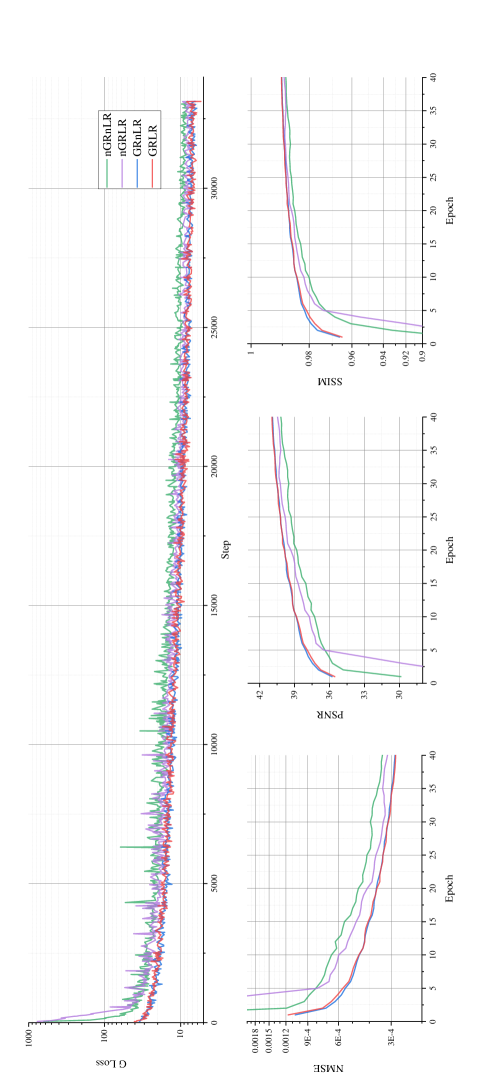

In this experiment, the effect of residual learning in the network was discussed. Our proposed model was tested on MICCAI 2013 grand challenge dataset, using Gaussian 1D 30% downsampling.

The experiment was divided into four groups: (1) GRLR (model with GR and LR), (2) GRnLR (model with GR without LR), (3) nGRLR (model with LR without GR), (4) nGRnLR (model without LR and GR). Early stopping strategy was turned off in this experiment to prolong the training process for a better and more distinguishable comparison for the training step.

Fig. 12 shows NMSE, SSIM, PSNR and generator loss (G Loss) of the four groups changing with the training process, and Fig. 13 shows testing examples with respect to different epoch weights.

Models with GR (GRLR, GRnLR) have faster convergence and better final results compared with those without GR (nGRLR, nGRnLR). If the model applies GR, then using LR has little further impact effect on the results. For non-GR models, nGRLR converges significantly slower than nGRnLR but final results are superior. Therefore, we chose GRLR as the generator for subsequent study.